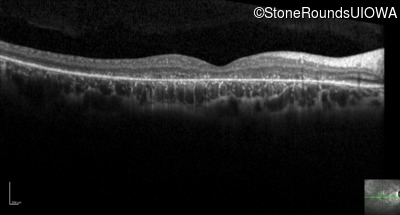

Optical Coherence Tomography - Right - 20/200 -3

Exemplar / OCT Stack

OCT Stack